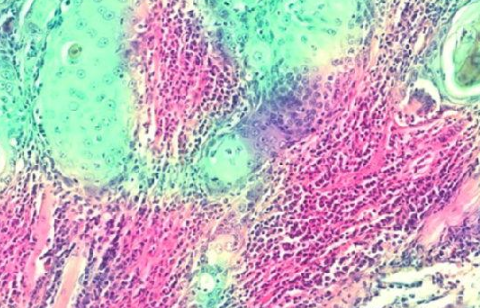

基于人工智能的区域检测包含肿瘤细胞和免疫细胞,分别以绿色和粉红色显示口腔癌在南亚最为普遍,特别是印度、巴基斯坦和斯里兰卡,主要原因是咀嚼烟草、食用槟榔和HPV等病毒感染。

那么具体怎么预测呢?研究人员成功地开发了一个可以测量肿瘤浸润淋巴细胞TILs的数字记分人工智能系统。TIL的存在越多,口腔癌几率越高。

这些图像是由巴基斯坦纪念癌症医院研究中心的病人扫描产生的,他们都已经接受了辐射和头颈外科手术。然后,癌症组织样本被送到英国华威大学,在那里,研究人员利用一种先进的成像机器,能够在微观范围内数字化地产生高分辨率的样本图像。

肿瘤细胞附近淋巴细胞的存在不仅有助于判断肿瘤具体的期限,还可用于准确预测肿瘤的进展。